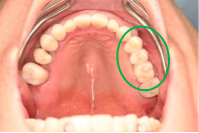

男性 Kさん 60代 (インプラント)

主訴

下の左右歯がないところに歯を入れたい。

治療内容

左右それぞれ3本歯がないところに2本ずつインプラントを埋入しました。

所感

上と下の歯の咬合接触がないすれ違い咬合です。上下義歯で対応するには最も難しいタイプの欠損状況です。治療開始前は、上下部分入れ歯が入っていましたが、入れ歯の安定が悪く、あちこちの歯茎に入れ歯が当たって痛く、満足に噛める状態ではありませんでした。上顎は、残ってる歯を活用するマグネット式総義歯を、下顎はインプラントを提案しました。上顎は、現在残っている歯の根管治療中です。上顎にマグネット式総義歯がはいれば、何でも食べられるようになります。

インプラント4本:¥363,000×4本=¥1,452,000(税込)

ポンティック2本:¥115,500×2本=¥231,000(税込)

合計:¥1,683,000(税込)

Before

▼初診時に使用していた部分入れ歯を装着したところ

▼インプラント埋入前

After

▼インプラント埋入後